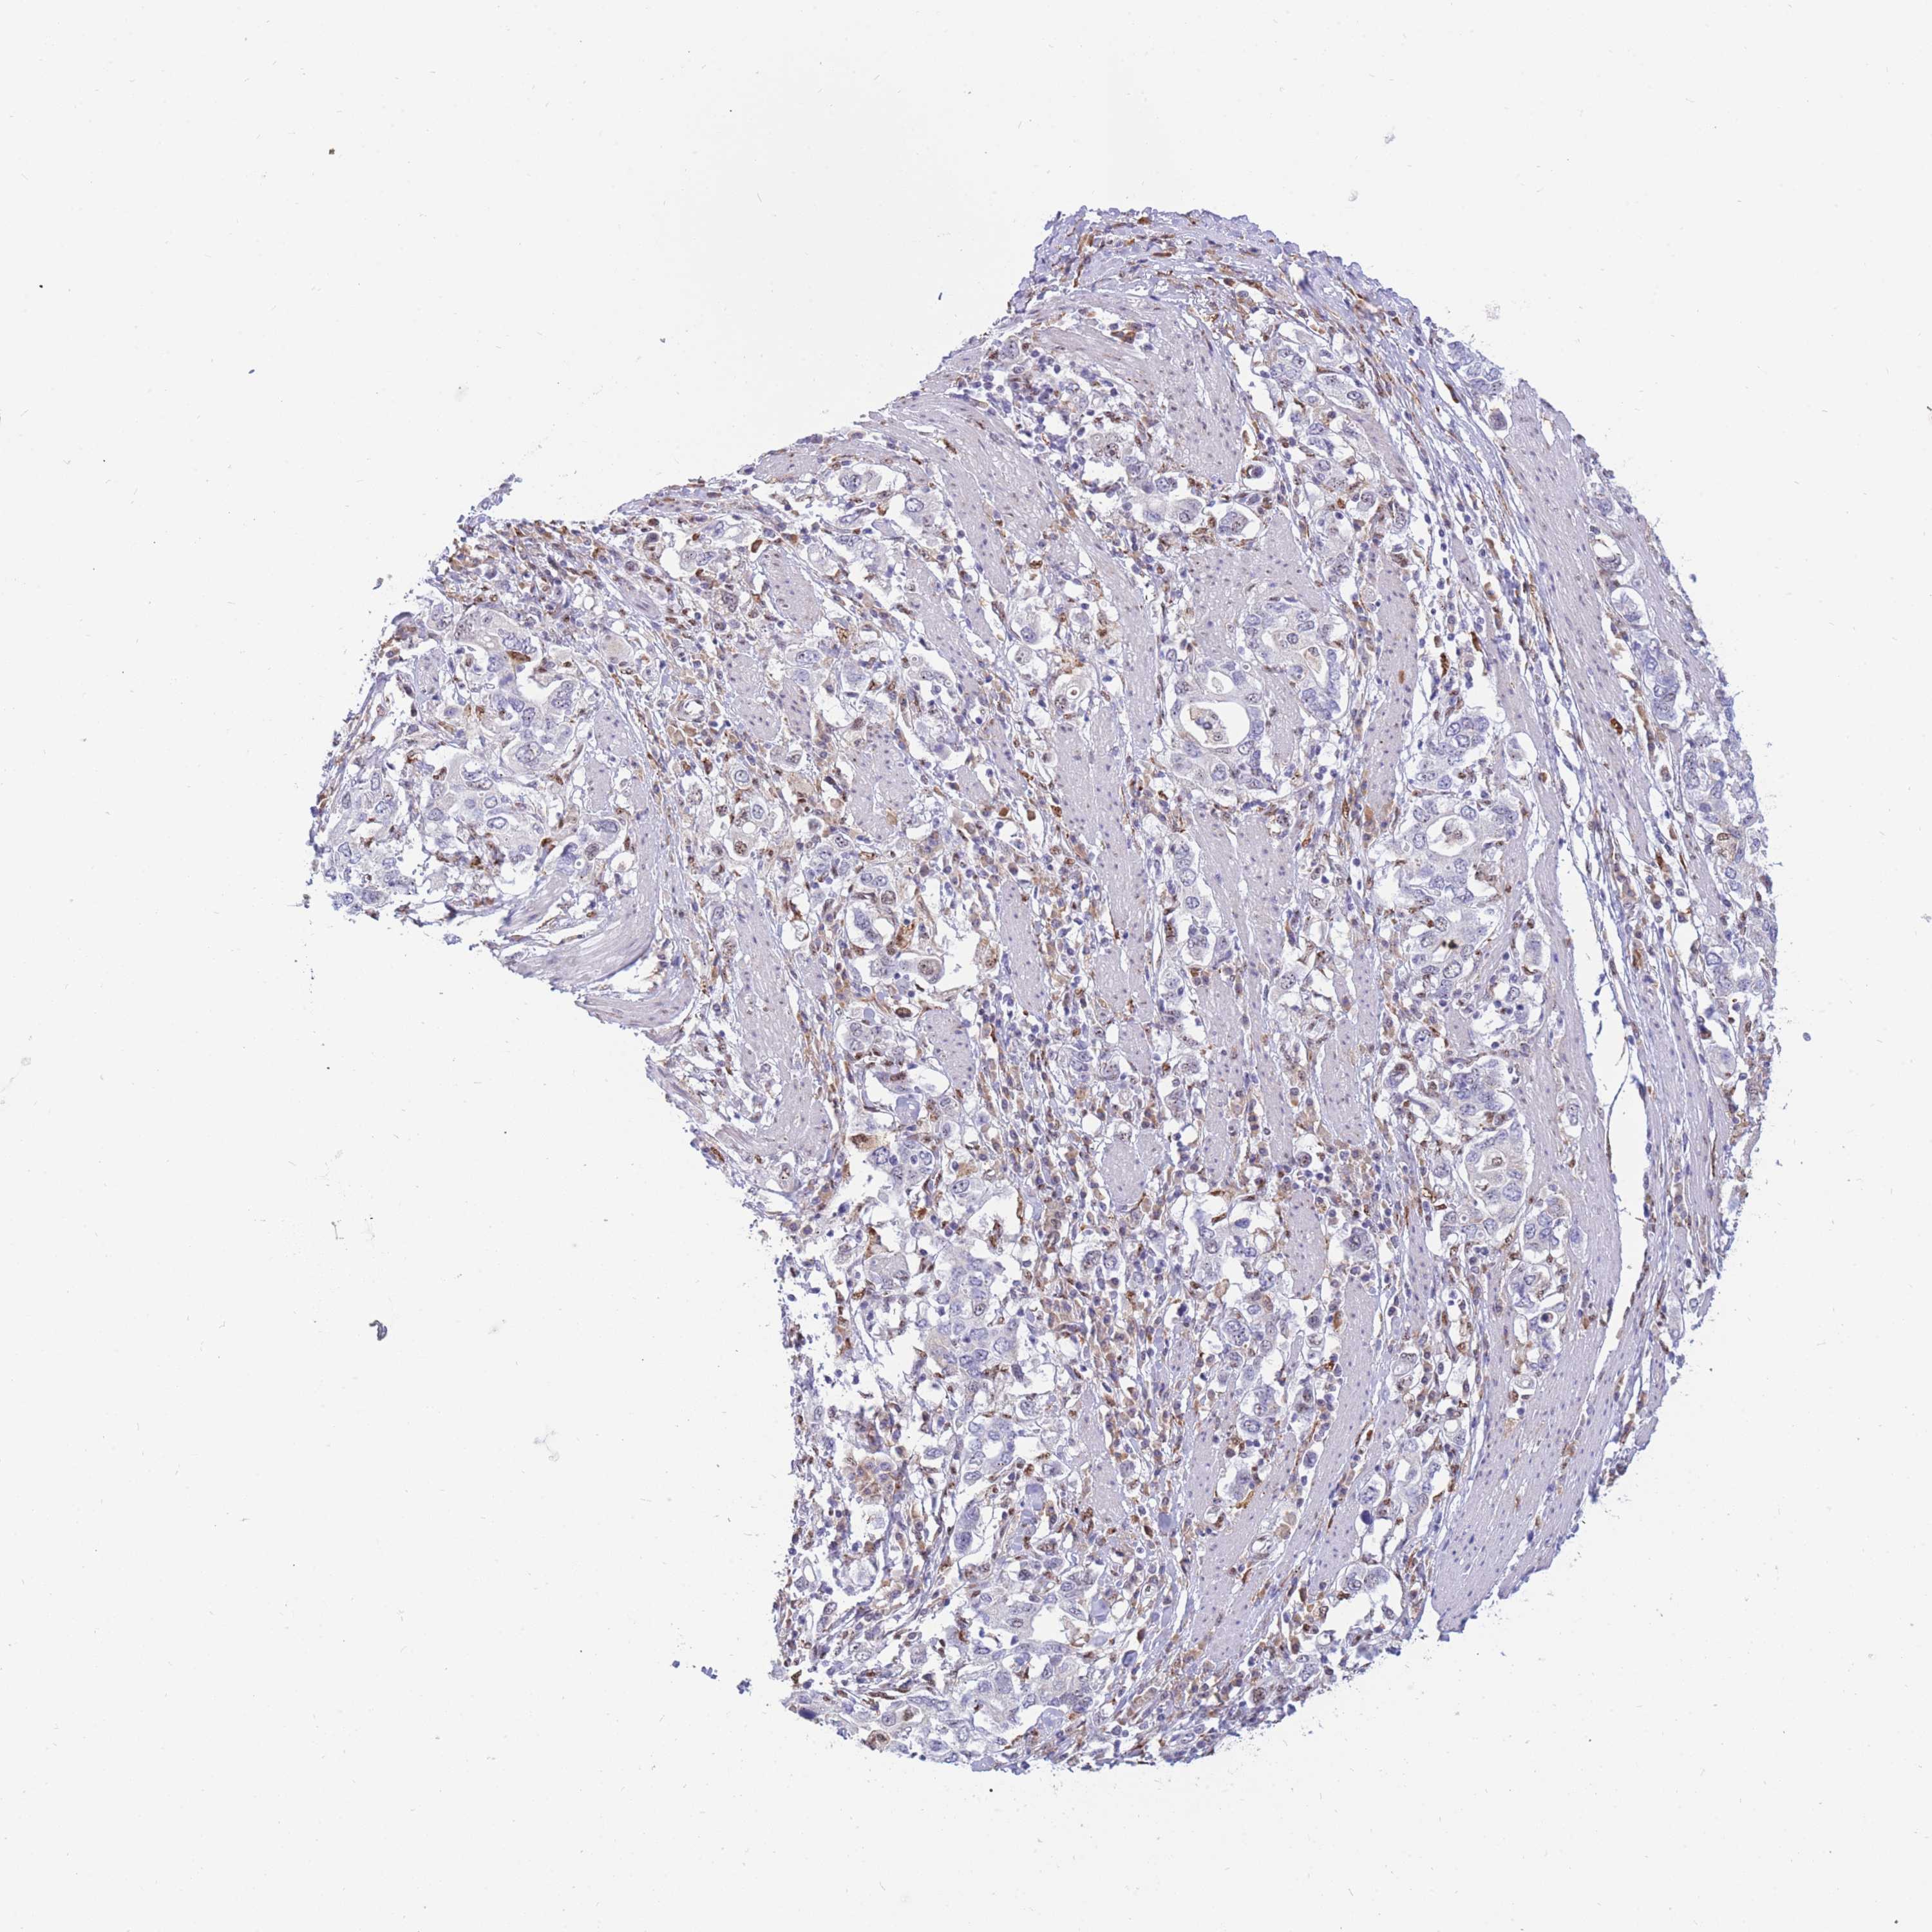

STOMACH CANCER - Protein expressioni

A mouse-over function shows sample information and annotation data. Click on an image to view it in a full screen mode. Samples can be filtered based on level of antibody staining by selecting one or several of the following categories: high, medium, low and not detected. The assay and annotation is described here.

Note that samples used for immunohistochemistry by the Human Protein Atlas do not correspond to samples in the TCGA dataset.

Antibody stainingi

Antibody staining in the annotated cell types in the current human tissue is reported as not detected, low, medium, or high, based on conventional immunohistochemistry profiling in selected tissues. This score is based on the combination of the staining intensity and fraction of stained cells.

Each image is clickable and will lead to virtual microscopy that enables deeper exploration of all samples and also displays staining intensity scores, fraction scores and subcellular localization as well as patient and tissue information for each sample.

HPA042585

HPA044022

HPA046691

HPA052337

HPA055498

Adenocarcinoma, NOS